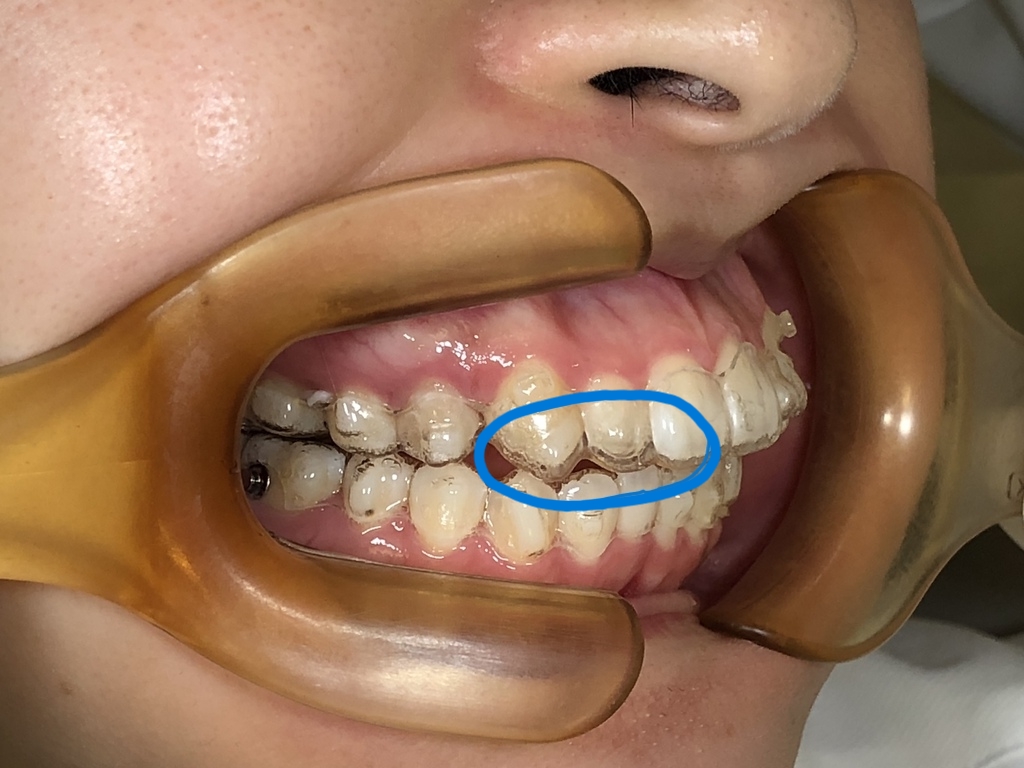

- マウスピースが明らかに浮いている

- 追加アタッチメント

- マウスピースの作り直し(リファインメント)